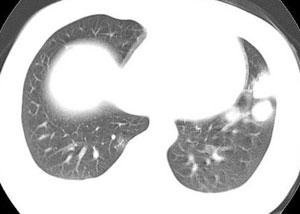

女性,30岁。

病史为胸痛20多天,无畏寒发热,无消瘦,无咳嗽咳痰。总之症状很逍遥。

临床以胸痛待查收住入院。

双肺野可见散在大小不等结节及肿块影,内密度不均匀,边缘部分清,部分欠清,纵隔未见明显肿大淋巴结.右侧胸腔少理积液.结合临床,考虑韦格肉芽肿可能吧,巨淋巴增生,结节病,特殊感染都要考虑.转移瘤临床不象.

2.肺ct表现为两肺多发大小不等结节影,大结节位于肺尖部,小结节多位于肺外带胸膜下,大结节内可见支气管充气征,周围可见月晕征(指在结节状或肉芽肿样病灶周围呈环形磨玻璃影),右肺门及腔静脉后可见小淋巴结,右侧胸腔内少量液体。

两肺散在分布大小不等的肿块及结节影,边缘毛糙,有分叶、毛刺,病灶密度不均匀,可见支气管充气相与空泡征。病变大多位于胸膜下,可见胸膜凹陷及胸腔积液。气管腔静脉间可见小结节影。

病人临床仅为胸痛,暂不考虑感染性病变。

考虑多发结节型细支气管肺泡癌。